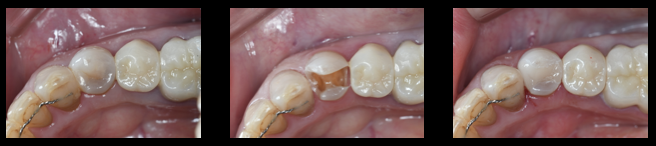

ケース1:銀の詰め物(メタルインレー)と歯との間に隙間ができ、虫歯になった歯をセレック(CEREC)を用いて即日オールセラミック修復治療をおこなったケース!!

写真左:術前の写真

写真中:虫歯除去後の状態(形成後)

写真右:術後の写真